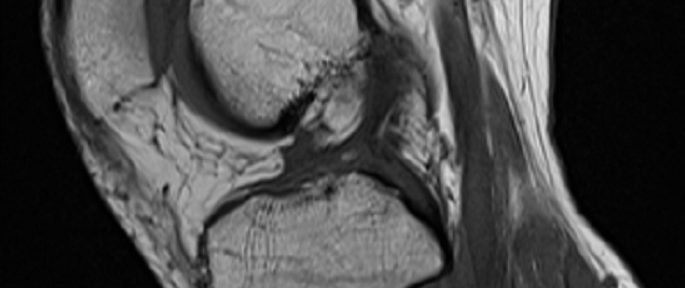

2021年12月2日、格闘技の練習中に左膝を捻った。2週間後にMRI撮影を行い、以下のように診断された。

左膝前十字靭帯損傷

内側半月板損傷

MRIの評価

断裂した前十字靭帯の脛骨側、大腿骨側の断端は共に、後十字靭帯と癒合しているように見える。前十靭帯の断端同士が癒合するという、理想的な自然治癒は起こらなかったが、後十字靭帯と癒合することで、膝の安定性を再獲得したケースである。内側半月板は、内縁部のみの損傷が外縁部まで広がり、血流の多いレッドゾーンに達したことから、今後、自然治癒することが期待できる。